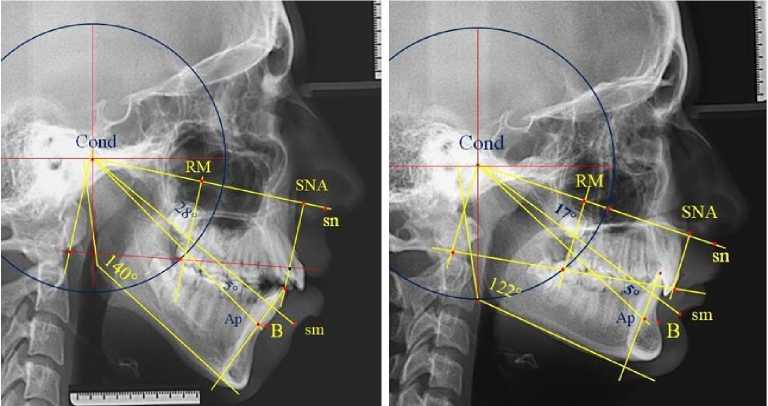

Кроме того, проведенный анализ положения резцов относительно окклюзионной линии позволил диагностировать положение резцов верхней и нижней челюсти и определять тактику лечения. При этом использовалась методика построения суставного круга, радиус которого составлял 2/3 от кондилярно-спинального расстояния (Cond-SNA). Точка пересечения перпендикуляра от середины линии Cond-SNA с контуром суставного круга определяло положение молярной окклюзионной точки. Высота молярного перпендикуляра служила ориентиром для определения передней и зад- ней точки с использованием коэффициента 1,2. Соединение передней, молярной и задней окклюзионных точек определяло положение окклюзионной линии.

Таким образом, изменение величины угла гнатической части лица ( sn-Cond-sm ) может быть диагностическим критерием оценки вертикальных аномалий окклюзии. Относительная стабильность положения апикально-кондилярной линии определяет положение апикальной точки нижнего медиального резца и проекцию верхушки корня на нижнечелюстную кость.

Результаты исследования позволили разработать метод исследования гнатической части лица и определение положения нижней точки апикального базиса по Schwarz на латеральной телерентгенограмме.

Метод основан на построении суназально-кондилярно-супраментального угла, величина которого является относительно стабильной величиной вне зависимости от типологических особенностей роста челюстей и составляет в среднем 20°. Данный показатель может быть использован в качестве диагностики аномалий в вертикальном направлении.

Кроме того, разработан метод определения положения апикальной точки нижней челюсти по Schwarz, основанный на построении суб-назально-кондилярно-апикального угла, равного 5°. Расстояние от режущего края до конструктивной апикальной точки нижнего резца соответствует расстоянию от режущего края резца до конструктивной точки В по Schwarz, определяющей проекцию верхушки корня на кость.

Указанный метод определения нижней апикальной точки позволяет более точно проводить анализ телерентгенограмм по Schwarz для дифференциальной диагностики гнатических и зубоальвеолярных форм аномалий окклюзии.